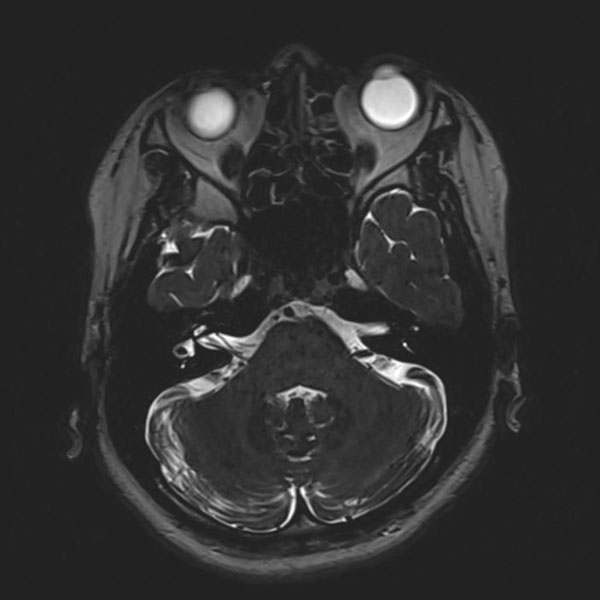

症例 '26年4月

No.

588

手術医師

手術年月

年齢

病名

術式

手術前

減圧前

減圧後

手術後

京都府の病院

'26年4月

40代

右三叉神経痛

(顔面の痛みをとること)

術後血管撮影